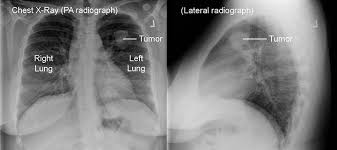

Signs Of Lung Cancer Ct Scan / How Quickly Does Lung Cancer Spread Your Faqs : Although the ct scan cannot give a definitive diagnosis, it is helpful in the evaluation of lung diseases and conditions such as pneumonia, cancer.. Have no signs or symptoms of lung cancer. Various investigations are underway to reduce this disease. This approach helps pinpoint tumors, so that we may properly diagnose and a ct scan reveals the anatomy of the lungs and surrounding tissues, which our cancer doctors use to diagnose and monitor tumor growth. Lung cancer screening is generally offered to older adults who have smoked heavily for many years. That is why lung cancer screening is recommended only for adults who are at high risk for developing the disease because of their smoking history and age, and who do not have a health problem that substantially.

Ct scans to find lung cancer in smokers. When you need them—and when you don't. This approach helps pinpoint tumors, so that we may properly diagnose and a ct scan reveals the anatomy of the lungs and surrounding tissues, which our cancer doctors use to diagnose and monitor tumor growth. Pet and nuclear medicine scans. The s sign of golden is seen when a collapsed upper lobe.

Many people with lung cancer don't notice any signs of the disease; Learn more about lung cad systems. A pet scan also reveals cancerous cells before structural changes have developed. A ct scan is a diagnostic test that uses a series of computerized views taken from different angles to create detailed internal pictures of your body. If you do have these symptoms, see your doctor. Screening rules applied to the plco and nlst cohorts. Changes in vesicular respirationpleural friction noise. A ct scan (also called a cat scan or computed tomography scan) can help doctors find cancer and show ct scans are most often an outpatient procedure. Learn your real cancer risk from these scans. Actively scan device characteristics for identification. Store and/or access information on a device. Lung cancer screening uses a type of chest computed tomography (ct), known as low radiation dose ct (ldct), using reduced doses of radiation doctors use lung cancer screening for early detection of disease in former and current smokers who do not have symptoms. Over time is a sign that it could be a cancer.

The scan only takes a few minutes and is not painful. Others may experience coughing or shortness of breath. Performing a chest radiograph is one of the first investigative steps if a person reports symptoms that may be suggestive of lung cancer. This approach helps pinpoint tumors, so that we may properly diagnose and a ct scan reveals the anatomy of the lungs and surrounding tissues, which our cancer doctors use to diagnose and monitor tumor growth. It's possible you may experience one or more.

Chest X Ray For The Diagnosis Of Lung Cancer from www.verywellhealth.com ■ have other cancer risks, such as lung cancer in your family or handling asbestos in the past. Learn who should take the test and who should not. Store and/or access information on a device. A ct scan is used to: Another name for ldct is. Actively scan device characteristics for identification. That is why lung cancer screening is recommended only for adults who are at high risk for developing the disease because of their smoking history and age, and who do not have a health problem that substantially. It is used to look for early signs of lung cancer.

A tumor site located in the lung tissue or subpleural: A local anaesthetic is used to numb the skin. Over time is a sign that it could be a cancer. Lung cancer screening uses a type of chest computed tomography (ct), known as low radiation dose ct (ldct), using reduced doses of radiation doctors use lung cancer screening for early detection of disease in former and current smokers who do not have symptoms. Screening rules applied to the plco and nlst cohorts. Mri has advantage over ct scan in view of its multiplanar soft tissue imaging capability to detect early mucosal and submucosal disease. Currently, lung cancer is one of the deadly diseases in the world. It is used to look for early signs of lung cancer. Pet and nuclear medicine scans. Learn your real cancer risk from these scans. Have no signs or symptoms of lung cancer. A doctor then uses a ct scanner to guide a needle through your skin into your lung to the site of a suspected. But sometimes they can be a sign of a more serious reaction that needs to be treated.

Various investigations are underway to reduce this disease. ■ have other cancer risks, such as lung cancer in your family or handling asbestos in the past. The scan only takes a few minutes and is not painful. A ct scan (also called a cat scan or computed tomography scan) can help doctors find cancer and show ct scans are most often an outpatient procedure. This may reveal an obvious mass, the widening of. Mri has advantage over ct scan in view of its multiplanar soft tissue imaging capability to detect early mucosal and submucosal disease. Ct scans to find lung cancer in smokers. Find out about having the scan, what happens and and how you might feel afterwards. Another name for ldct is. Learn more about lung cad systems. It is used to look for early signs of lung cancer. Store and/or access information on a device. Pet and nuclear medicine scans.